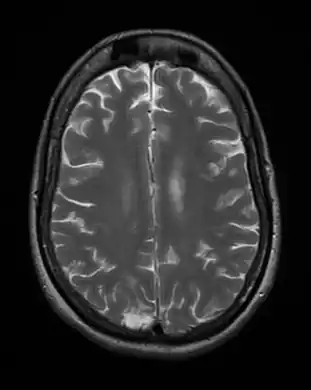

-

Cerebral toxoplasmosis (with primary involvement in the right occipital lobe) -

Cerebral toxoplasmosis -

Cerebral toxoplasmosis

Acute toxoplasmosis is often asymptomatic in healthy adults.[13][14] However, symptoms may manifest and are often influenza-like: swollen lymph nodes, headaches, fever, and fatigue,[15] or muscle aches and pains that last for a month or more. It is rare for a human with a fully functioning immune system to develop severe symptoms following infection. People with weakened immune systems are likely to experience headache, confusion, poor coordination, seizures, lung problems that may resemble tuberculosis or Pneumocystis jiroveci pneumonia (a common opportunistic infection that occurs in people with AIDS), or blurred vision caused by severe inflammation of the retina (ocular toxoplasmosis).[15] Young children and immunocompromised people, such as those with HIV/AIDS, those taking certain types of chemotherapy, or those who have recently received an organ transplant, may develop severe toxoplasmosis. This can cause damage to the brain (encephalitis) or the eyes (necrotizing retinochoroiditis).[16] Infants infected via placental transmission may be born with either of these problems, or with nasal malformations, although these complications are rare in newborns. The toxoplasmic trophozoites causing acute toxoplasmosis are referred to as tachyzoites, and are typically found in bodily fluids.[17][18]